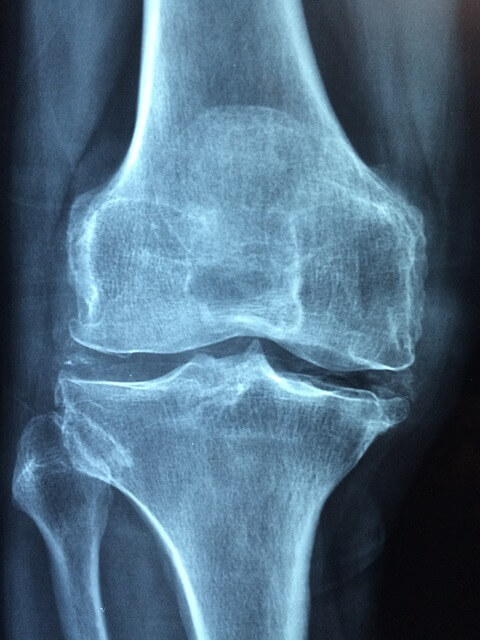

▶ 관절염

무릎관절의 염증으로 인해 발생하는 통증,고령자,비만,부상, 유전적 요인등 다양합니다.

▶퇴행성 변화

나이가 들어감에 따라 무릎관절의 퇴행성 변화가 발생할 수 있습니다. 잘못된 자세 반복된 자세 등이 원인입니다.